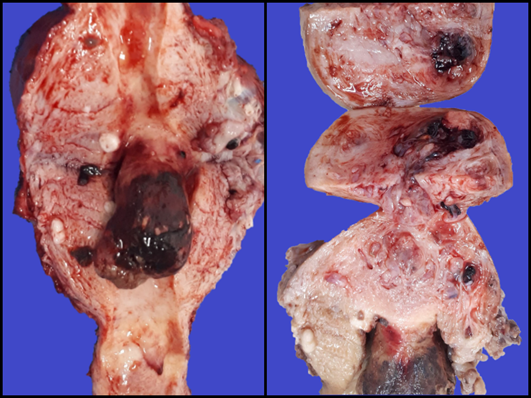

Le realizaron histerectomía con salpingooforectomía izquierda. En el laboratorio de Patología, al estudio macroscópico del espécimen quirúrgico, se observó una lesión polipoide de color violáceo con áreas necrosadas y hemorrágicas, que dependía del fondo uterino y medía 4 x 3 x 2,5 cm. Al corte del pólipo, se observaron múltiples estructuras vasculares congestivas, algunas de ellas con trombos intraluminales; estos vasos sanguíneos anormales también comprometían focalmente el miometrio, en el área subyacente a la localización del pólipo (Figura 1). Adicionalmente, se identificaron nodulaciones intramurales sugestivas de leiomiomas.